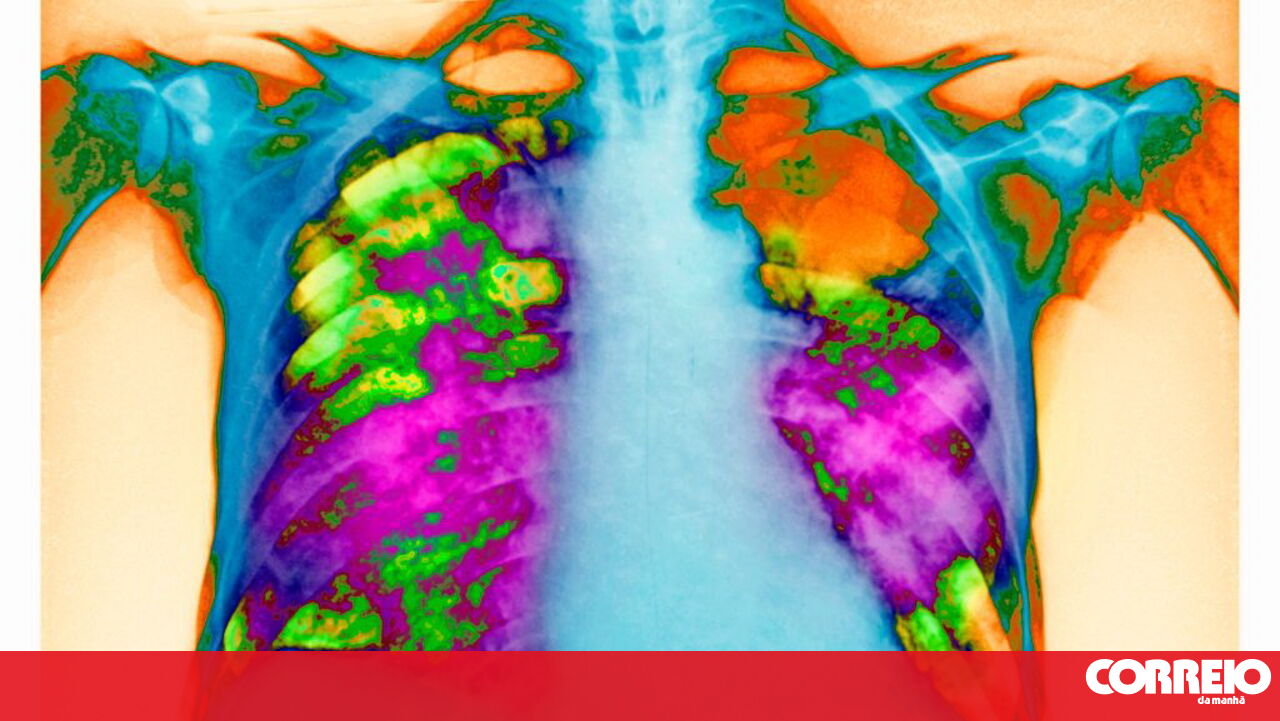

O que é a pneumonia?

A pneumonia é causada por bactérias, vírus ou fungos. Conheça os sintomas.

A pneumonia consiste numa inflamação aguda do tecido pulmonar, em particular dos alvéolos, os "sacos de ar" do pulmão. Devido à inflamação, ficam preenchidos com líquido não conseguindo realizar as trocas gasosas em que consiste a respiração.